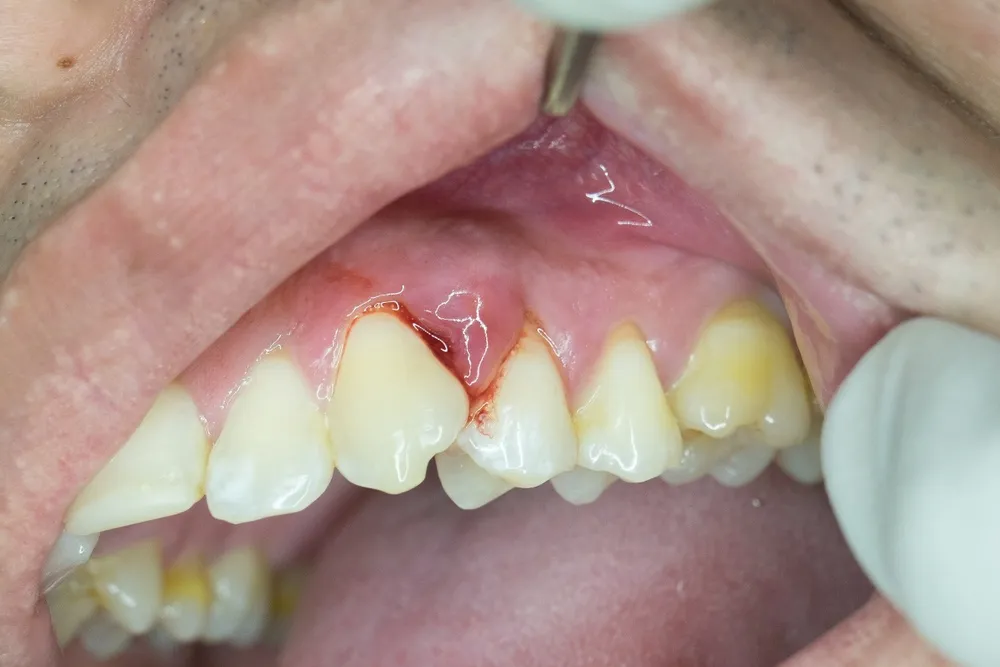

Tình trạng sưng nướu răng hàm trên hay được gọi là sưng lợi vùng hàm trên, là là một bệnh lý răng miệng tưởng chừng đơn giản. Tuy nhiên thực chất bệnh này tiềm ẩn nhiều yếu tố phức tạp. Tuy nhiên, một số người không được thăm khám và điều trị đúng phương pháp, kịp thời. Điều này có thể gây hậu quả nghiêm trọng cho răng mình sau này. Khi mô nướu bị tổn thương, hệ thống miễn dịch tại chỗ sẽ phản ứng lại với vi khuẩn. Đây chính là tác nhân chính gây viêm nướu răng

Quá trình viêm nhiễm này dẫn đến hàng loạt biểu hiện lâm sàng nguy hiểm. Ví dụ như sưng nề mô mềm, tấy đỏ, cảm giác đau nhức. Thậm chí trong một số trường hợp có thể xuất hiện mủ hoặc mùi hôi khó chịu. Những triệu chứng này không chỉ ảnh hưởng đến chức năng ăn nhai. Nó còn gây cản trở trong sinh hoạt hằng ngày. Từ đó làm giảm chất lượng cuộc sống của người bệnh.

Biểu hiện tình trạng sưng nướu răng hàm trên tương tự như viêm nướu. Cụ thể chúng thường đi kèm với một số triệu chứng đặc trưng, dễ nhận biết. Việc nắm bắt sớm những dấu hiệu này rất quan trọng. Chúng sẽ là căn cứ giúp người bệnh chủ động hơn trong việc thăm khám và điều trị. Thông qua đó đó ngăn ngừa các biến chứng nguy hiểm có thể xảy ra.

Cụ thể bệnh sưng nướu hàm trên có những biểu hiện sau

- Vùng nướu bị sưng thường chuyển sang màu đỏ tươi hoặc đỏ sẫm. Thay vì màu hồng nhạt như nướu khỏe mạnh.

- Người bệnh có thể cảm thấy đau rát, khó chịu, đặc biệt khi chạm nhẹ, ăn uống hoặc đánh răng.

- Nướu dễ bị chảy máu trong quá trình đánh răng, dùng chỉ nha khoa. Thậm chí bị ngay khi ăn các món cứng, cay, mặn.

- Nướu bị co rút do viêm, khiến phần chân răng lộ rõ. Thông qua đó làm răng trông dài bất thường và dễ ê buốt.

- Vùng nướu có thể xuất hiện ổ mủ, gây sưng lớn. Đồng thời gây đau nhức dữ dội và kèm theo mùi hôi miệng khó chịu.

- Viêm nướu kéo dài khiến nướu tách rời khỏi răng, tạo khe hở nơi vi khuẩn dễ tích tụ. Từ đó làm gia tăng nguy cơ viêm nha chu và mất răng nếu không được điều trị kịp thời.